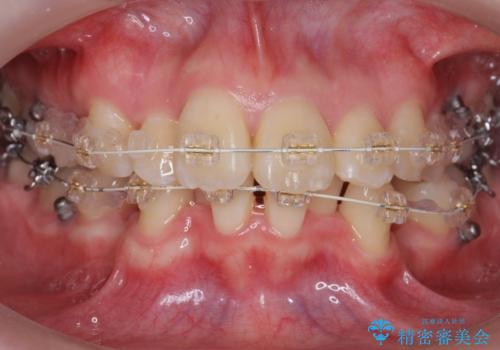

20代女性 前から5番目の歯を抜歯

- 前歯のがたつき、前突を主訴に来院。

通常前から4番目の歯を抜歯するのですが、左上5番の形が矮小であったため、そちらを抜歯しました。(患者様の希望にそっています。)

前から5番目の歯を抜くと、長くて1年ほど矯正期間が延長しますが、形に異常がない左上4番を抜かずに保存しています。

治療は長くかかりましたが、正常な形の歯をのこすことができました。